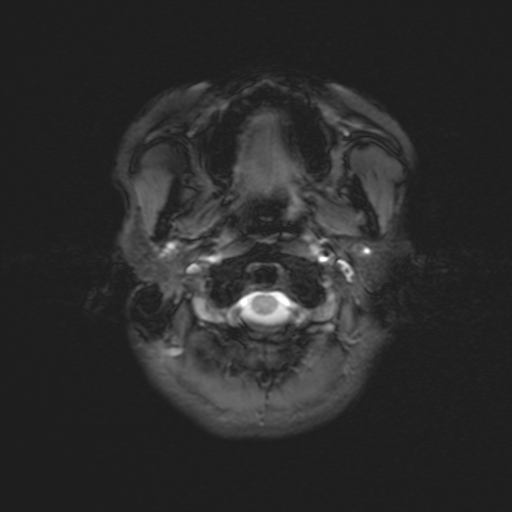

Descrizione Serie: pd+t2_tse_tra_p2

Modalità: MR